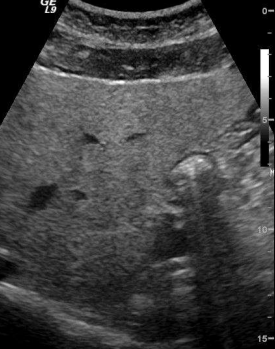

<p>Artefacto más evidente en este quiste</p>

Artefacto más evidente en este quiste

Refuerzo acústico posterior